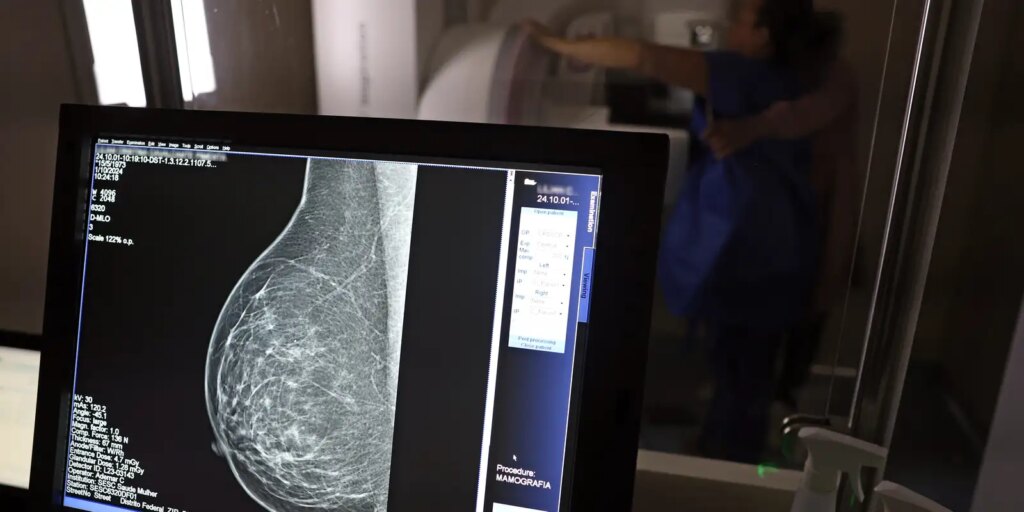

O direito já estava incluído na CLT desde 2018. A partir de agora, as empresas passam a ser obrigadas a divulgar essa informação, além de outras relacionadas a campanhas oficiais de vacinação contra o HPV e sobre o acesso a serviços de diagnósticos de cânceres de mama, próstata e de colo do útero.

O texto estende o uso das folgas também para a realização de exames preventivos do HPV, além dos de câncer que já estavam previstos na legislação anterior. A a Lei 15.377 foi sancionada pelo presidente Luiz Inácio Lula da Silva, e publicada na edição do Diário Oficial da União (DOU).